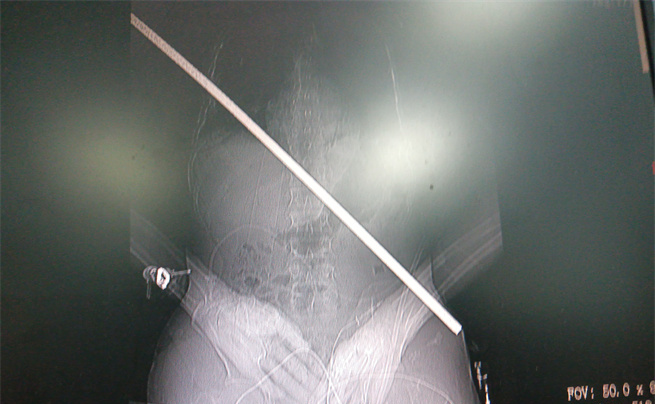

男子身上取出的鋼筋

“趕快救人!”工友們立即跑下來,檢查他的情況,只見鋼筋從右胸貫進身體,末端到達左下腹,把皮膚頂起,只差一點就完全穿透身體了。大家從未見過如此慘烈的受傷情景,在安撫龍成的同時,迅速撥打急救電話。

影像圖。大坪醫(yī)院供圖

術中,打開胸腔和腹腔,發(fā)現(xiàn)傷者右肺臟已被鋼筋穿透,鋼筋緊貼脊柱,隔肌、橫結(jié)腸及小腸系膜等被貫通,幸運地是鋼筋避開了心臟,從下腔靜脈后方、腹主動脈前方穿過。術中還由消化內(nèi)科文良志副教授行胃鏡檢查排除了食管損傷。放射影像科曹瑞、王承諾技師利用先進的移動CT在手術室行頭顱CT檢查進一步排除了嚴重的顱腦損傷。

由沈岳教授親自緩慢拔出體內(nèi)長達67厘米的鋼筋。隨后,各組專家各司其職,輪番上陣,為其修補好肺臟、隔肌、腸系膜等破損處。讓大家揪心的是,術中,病人曾雙側(cè)瞳孔變大,生命體征一度危急,經(jīng)醫(yī)生努力又將病人從鬼門關拉了回來。